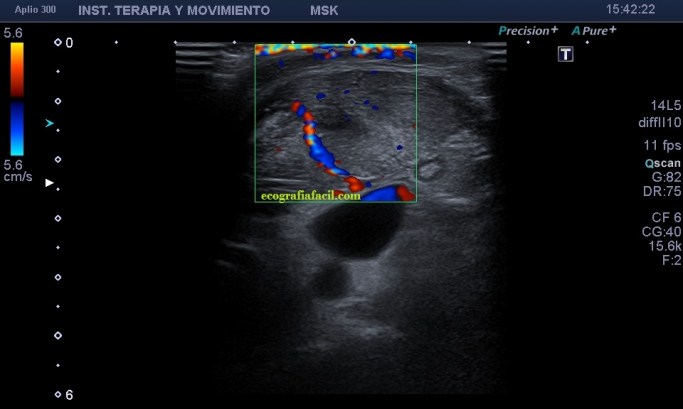

Parece existir señal Doppler periférica a la región anómala, que se extiende desde tercio medio del ECM, en su vertiente posterior hasta por lo menos la articulación esternoclavicular, aunque podría extenderse a la región infraclavicular.

Desde la imagen 1 hasta la 4 realizadas en eje corto, el ECM está afectado claramente, pero en la imagen 7 donde ves un corte en eje largo puedes observar como el tejido celular subcutáneo también ha cambiado su aspecto y no es hipoecogénico, sino que es ligeramente hiperecogénico y que corresponde en cercanía con la afectación infecciosa del músculo, ojo a todos lo detalles (ganglios incluidos), que el árbol no nos impida ver el bosque…